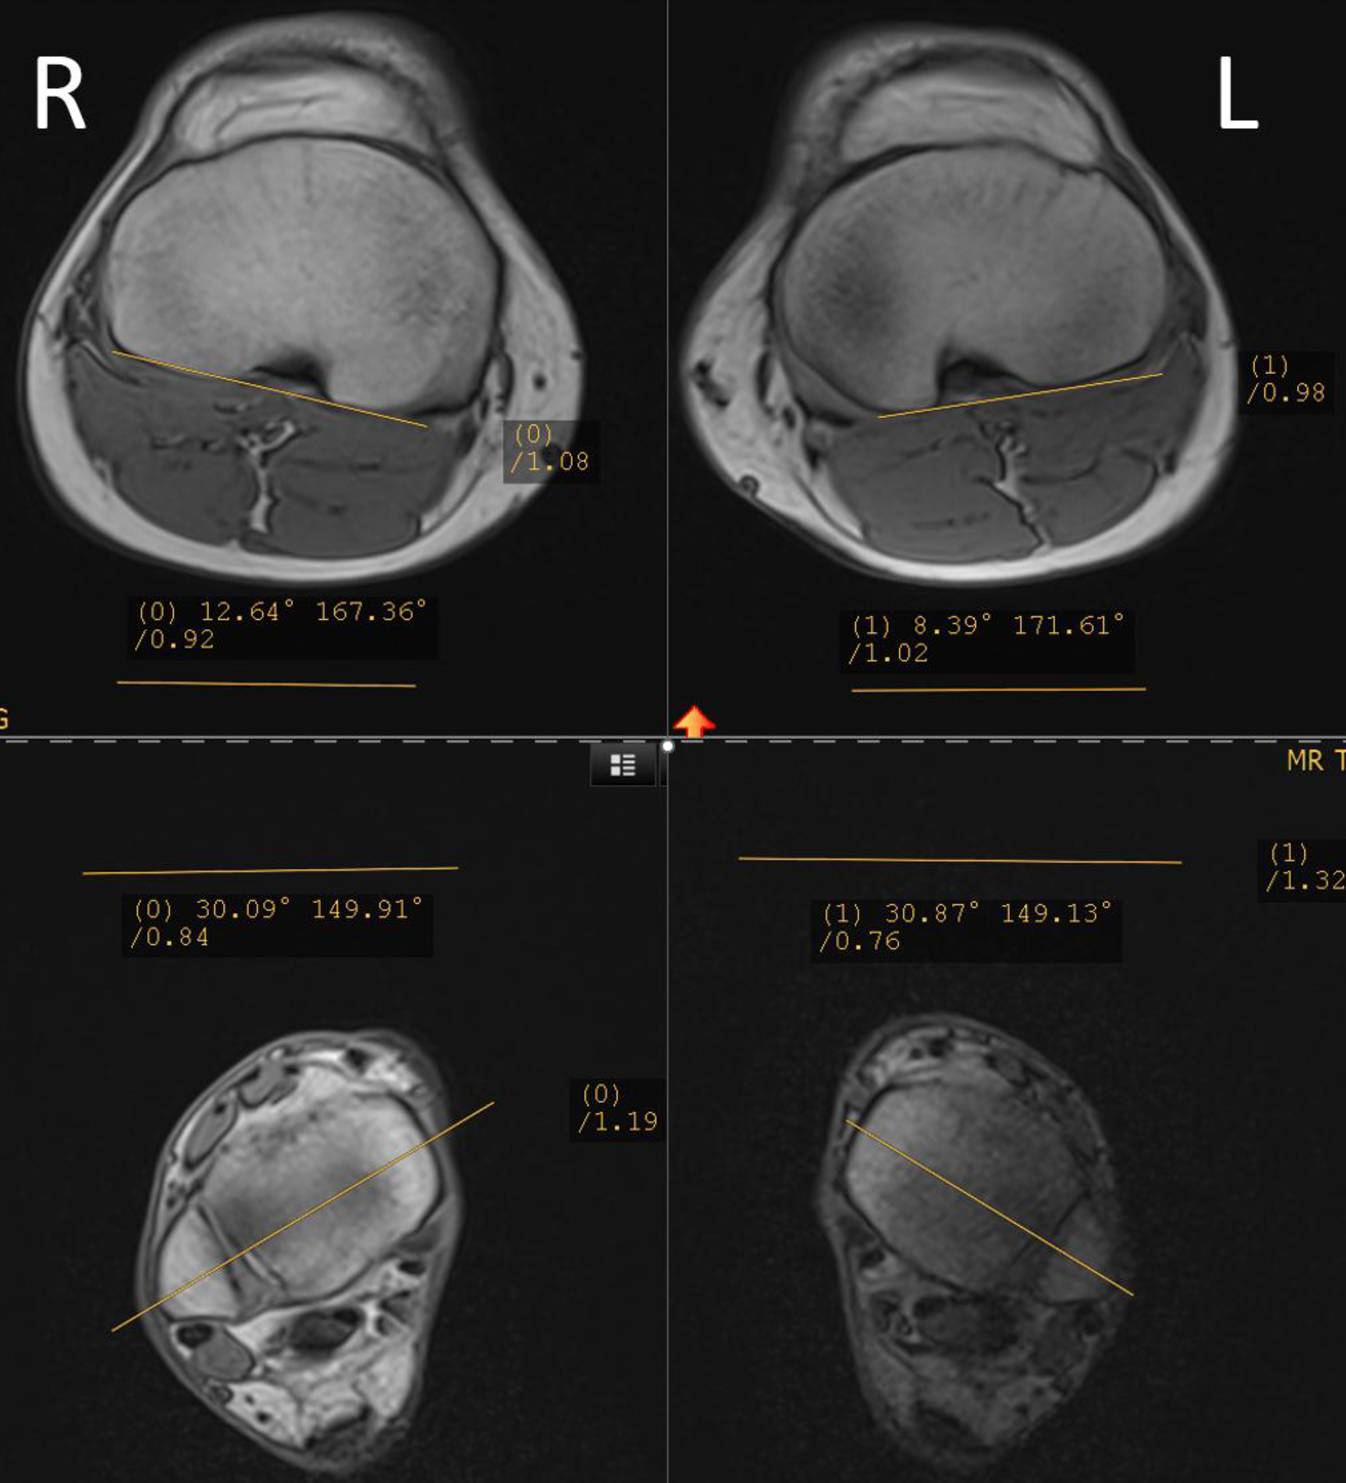

Bei Beschwerdepersistenz trotz mehrmonatiger Physiotherapie erfolgt eine Weiterabklärung der Torsion mittels Torsions-MRT der unteren Extremitäten und eine Röntgen-Ganzbeinaufnahme. In der Torsions-MRT bestätigt sich die erhöhte tibiale Außentorsion mit gemessen 43 und 39° links (Abb. 2). Für die Torsionsmessung wird tibial der Winkel zwischen der Transmalleolarachse direkt oberhalb des oberen Sprunggelenks und der Tangente an die posterioren Tibiakondylen direkt unterhalb der Kniegelenklinie verwendet [31, 36]. Auch bestätigt sich die erhöhte femorale Antetorsion mit rechts 30 und links 34° nach Murphy [27]. Im Ganzbeinbild zeigt sich bei nach innen gerichteter Patella eine gerade Beinachse (Abb. 3). Im „winking sign“ zeigt sich eine Überlagerung der lateralen Femurkondyle mit der lateralen Eminentia tibae, was bei korrekt zentrierter Ganzbeinaufnahme auf eine Torsionspathologie oder erhöhte Knieversion (intraartikuläre femorotibiale Rotation) hinweisen kann [12]. In diesem Fall zeigt sich keine erhöhte Knieversion in der Rotations-MRT, die intraartikuläre femorotibiale Rotation beträgt rechts 2 und links 6° (Norm < 10–15°). Der TT-TG-Abstand („tibial tuberosity – trochlear groove distance“) ist rechts mit 11 mm normwertig und links mit 20 mm grenzwertig erhöht.

Abb. 2

Tibiale Torsionsmessung in der Rotations-Magnetresonanztomographie beidseits. Gemessen wird der Winkel zwischen der Transmalleolarachse direkt oberhalb des oberen Sprunggelenks und der Tangente an den posterioren Tibiakondylen direkt unterhalb der Kniegelenklinie. (Mit freundl. Genehmigung, © T. Tondelli et al.)

Die in der Literatur am häufigsten beschriebene Messmethode der tibialen Torsion misst den Winkel zwischen der Transmalleolarachse direkt oberhalb des oberen Sprunggelenks und der Tangente an die posterioren Tibiakondylen direkt unterhalb der Kniegelenklinie ([31, 36]; Abb. 2). Der postulierte Normbereich der tibialen Torsion variiert zwischen den Studien [6, 13, 21, 35, 38], ein evidenzgestützter Grenzwert für eine operative Korrektur besteht nicht [31]. Wir verwenden daher einen Richtwert von 35° tibialer Außentorsion für eine Torsionsosteotomie, welcher teils auf anatomischen Studien [35] und teils auf in der Literatur als effektiv beschriebenen tibialen Torsionskorrektur basiert [31]. Die erhöhte femorale Anteversion als Risikofaktor für anterioren Knieschmerz ist im Rahmen einer Maltorsion und Patellainstabilität etabliert. Die Knieversion, definiert als statische Torsion der Tibia im Verhältnis zum Femur gemessen in voller Extension [16], erhöht damit die effektive Außentorsion der distalen Tibia im Vergleich zum Femur. Wir erachten eine Knieversion (d. h. intraartikuläre Außendrehung der proximalen Tibia zum distalen Femur) von 10–15° als erhöht [16]. Ein breit abgestützter Normbereich existiert nicht, die Knieversion wurde als möglicher Risikofaktor für eine Patellainstabilität [9] identifiziert und eine Assoziation mit anteriorem Knieschmerz berichtet [1, 11, 16]. Bei Vorliegen einer erhöhten Knieversion addieren wir diese zur tibialen Außentorsion und lassen den Wert in den Korrekturentscheid mit einfließen. In unserem Fallbeispiel war die Knieversion mit 2° tief und damit nicht ausschlaggebend.